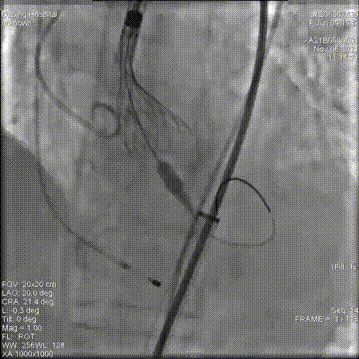

18mm球囊预扩

第一次释放,位置过高回收定位